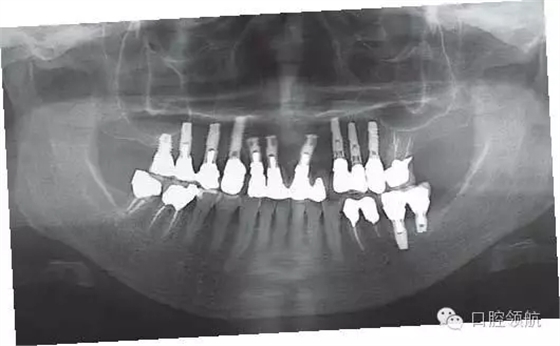

圖6 修復(fù)戴入后的全景X線片。